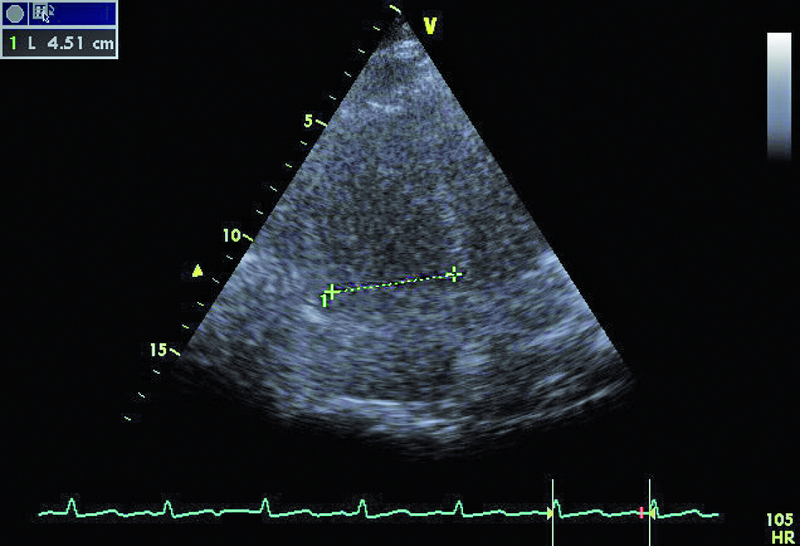

Powodem hospitalizacji 74-letniej kobiety był wielogodzinny ból w klatce piersiowej z towarzyszącą dusznością i niskim ciśnieniem tętniczym (90/60 mm Hg). W dniu hospitalizacji wystąpiło także krótkotrwałe omdlenie. W EKG zwracały uwagę cechy przebytego zawału serca ściany dolnej oraz brak progresji załamka R w odprowadzeniach V1-V4. Pacjentka od kilku lat chorowała na cukrzycę i nadciśnienie tętnicze. Po krótkotrwałym pobycie na oddziale szpitala rejonowego chorą przeniesiono do ośrodka referencyjnego. W wykonanej w trybie pilnym koronarografii uwidoczniono nieistotne zmiany miażdżycowe w naczyniach wieńcowych – maksymalnie do 40%. Wywiad, dziesięciokrotnie podwyższone stężenie d-dimeru i troponiny oraz powiększenie jamy prawej komory w badaniu echokardiograficznym stanowiły podstawę do poszukiwania zatorowości płucnej. Wykonane badanie TK klatki piersiowej pozwoliło uwidocznić skrzeplinę obejmującą pień oraz gałęzie płucne do poziomu tętnic segmentalnych. Ze względu na brak poprawy klinicznej w trakcie podawania heparyny zastosowano leczenie fibrynolityczne (alteplaza). Z powodu gorączki zastosowano także antybiotyk. W USG jamy brzusznej nie stwierdzono procesu nowotworowego, a badanie układu żylnego kończyn dolnych uwidoczniło skrzeplinę w żyle podkolanowej. Po kilku dniach od podania leku fibrynolitycznego obserwowano stopniowe ustępowanie duszności, stabilizację ciśnienia tętniczego, zmniejszenie parametrów zapalnych i stężenia d-dimeru. Rejestrowano także wzrost ciśnienia parcjalnego tlenu we krwi obwodowej. Dziesięć dni później wykonano kontrolne badanie echokardiograficzne (ryciny).

Dowodem klinicznym masywnej zatorowości płucnej był u chorej epizod omdlenia, utrzymująca się duszność, niskie ciśnienie tętnicze. Wiodącą rolę w rozpoznaniu choroby pełni tomografia komputerowa. Badanie echokardiograficzne uznawane jest za uzupełniające. Powiększenie jamy prawej komory stwierdzane w dniu hospitalizacji mówiło o możliwości istotnej dysfunkcji łożyska płucnego. Masywna zatorowość jest wskazaniem do włączenia leczenia fibrynolitycznego, zmniejszającego śmiertelność i zapobiegającego nawrotom choroby. Stan kliniczny pacjentki w wyniku zastosowanej alteplazy poprawił się. Rejestrowano zmniejszenie stężenia d-dimeru i troponiny. Czy jednak sytuacja chorej nie budzi już niepokoju? Mimo ograniczonej jakości przedstawionych rycin można dostrzec, że jama prawej komory jest przeciążona (ryc. 1, 2), a ciśnienie w łożysku tętnic płucnych szacowane z czasu akceleracji wypływu (66 ms!) jest podwyższone (ryc. 3). Im większa jest obstrukcja łożyska płucnego, tym więcej cech dysfunkcji prawej komory stwierdza się w badaniu ultradźwiękowym. Warunki obrazowania utrudniały odniesienie się do odcinkowej kurczliwości ściany wolnej i potwierdzenie lub wykluczenie objawu McConnella, czyli dysfunkcji segmentu środkowego. Ze względu na trudność w wizualizacji wsierdzia nie można było także ocenić zmiany pola powierzchni prawej komory (RV FAC). Mimo zachowanej funkcji kurczliwej prawej komory mierzonej wartością przemieszczenia pierścienia trójdzielnego (ryc. 4) uważny czytelnik z pewnością dostrzeże tkwiącą w prawej tętnicy płucnej skrzeplinę (ryc. 5, 6). Rzadko udaje się bezpośrednio uwidocznić skrzeplinę w łożysku tętnic płucnych. Kontrolne badanie TK klatki piersiowej potwierdziło obecność tzw. zatoru jeźdźca w pniu płucnym ze skrzeplinami w gałęzi prawej i gałęziach segmentalnych do płata dolnego prawego płuca. Obserwowano jedynie częściową regresję skrzeplin z tętnic płatowych i segmentalnych. Mamy więc do czynienia z nieskutecznością leczenia fibrynolitycznego (no clot resolution). Dobry stan kliniczny chorej nie wskazywał na potrzebę zastosowania leczenia chirurgicznego i embolektomii. Nie podjęto także decyzji o powtórnym leczeniu fibrynolitycznym z użyciem innego środka. Postanowiono kontynuować leczenie przeciwkrzepliwe i przeprowadzić po kilku tygodniach ponowną ocenę stanu klinicznego pacjentki i stanu łożyska tętnic płucnych. Wobec wieku chorej i licznych obciążeń internistycznych interesującą opcją leczenia (ale niestosowaną w tutejszym ośrodku) byłaby trombektomia za pomocą cewnika z miejscowym podaniem leczenia fibrynolitycznego.